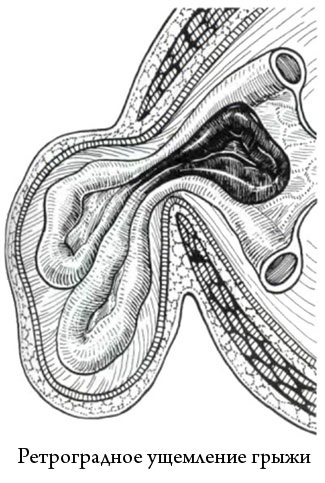

3. încălcarea retrogradă

Acest tip de încălcare se produce atunci când mai mult de o buclă a intestinului să încalce în inelul herniar, dar mai multe în același timp supus ischemiei acea parte a intestinului, care sunt situate între buclele dezavantajate.